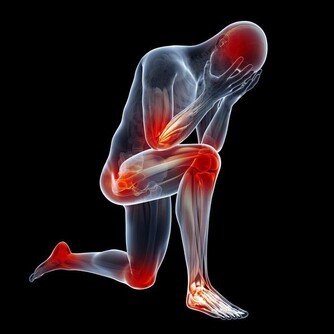

4、肝膽疾病

中醫認為,口乾、口苦是肝膽火旺的典型症狀。當人體的肝臟功能出現問題時,體內的代謝物、毒素、垃圾就不能及時排出並且堆積,從而引起口苦。

另外,很多時候,膽囊疾病病人都有口苦的現象。尤其是老年人,由於胃動力差或者膽汁反流所引起口苦。